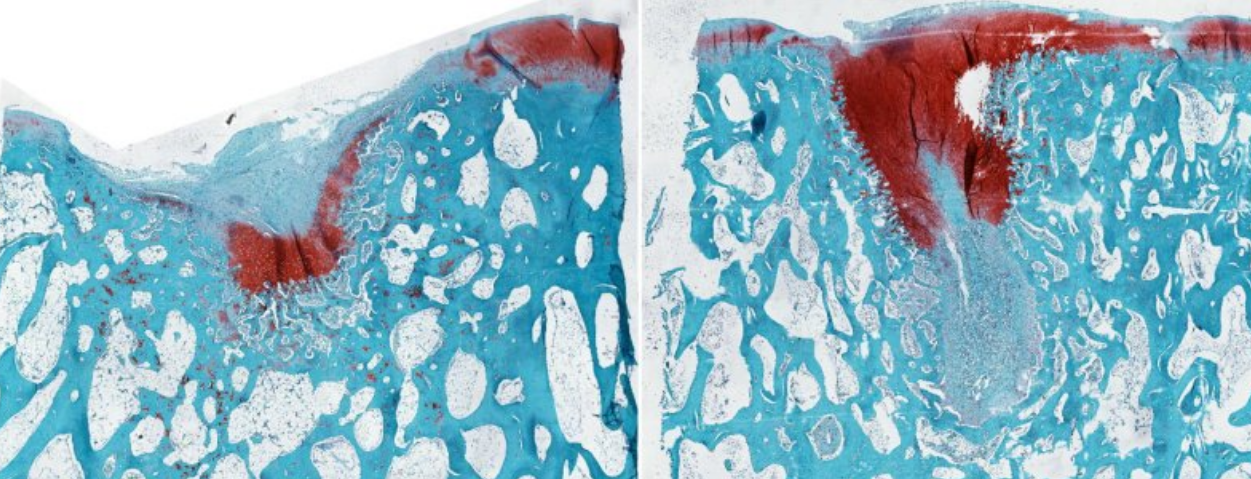

Resultados prometedores en modelos animales

El biomaterial fue aplicado a las rodillas de ovejas durante seis meses, logrando la regeneración de cartílago de alta calidad. Esto representa un avance sin precedentes, ya que hasta ahora la reparación completa del cartílago era prácticamente imposible.